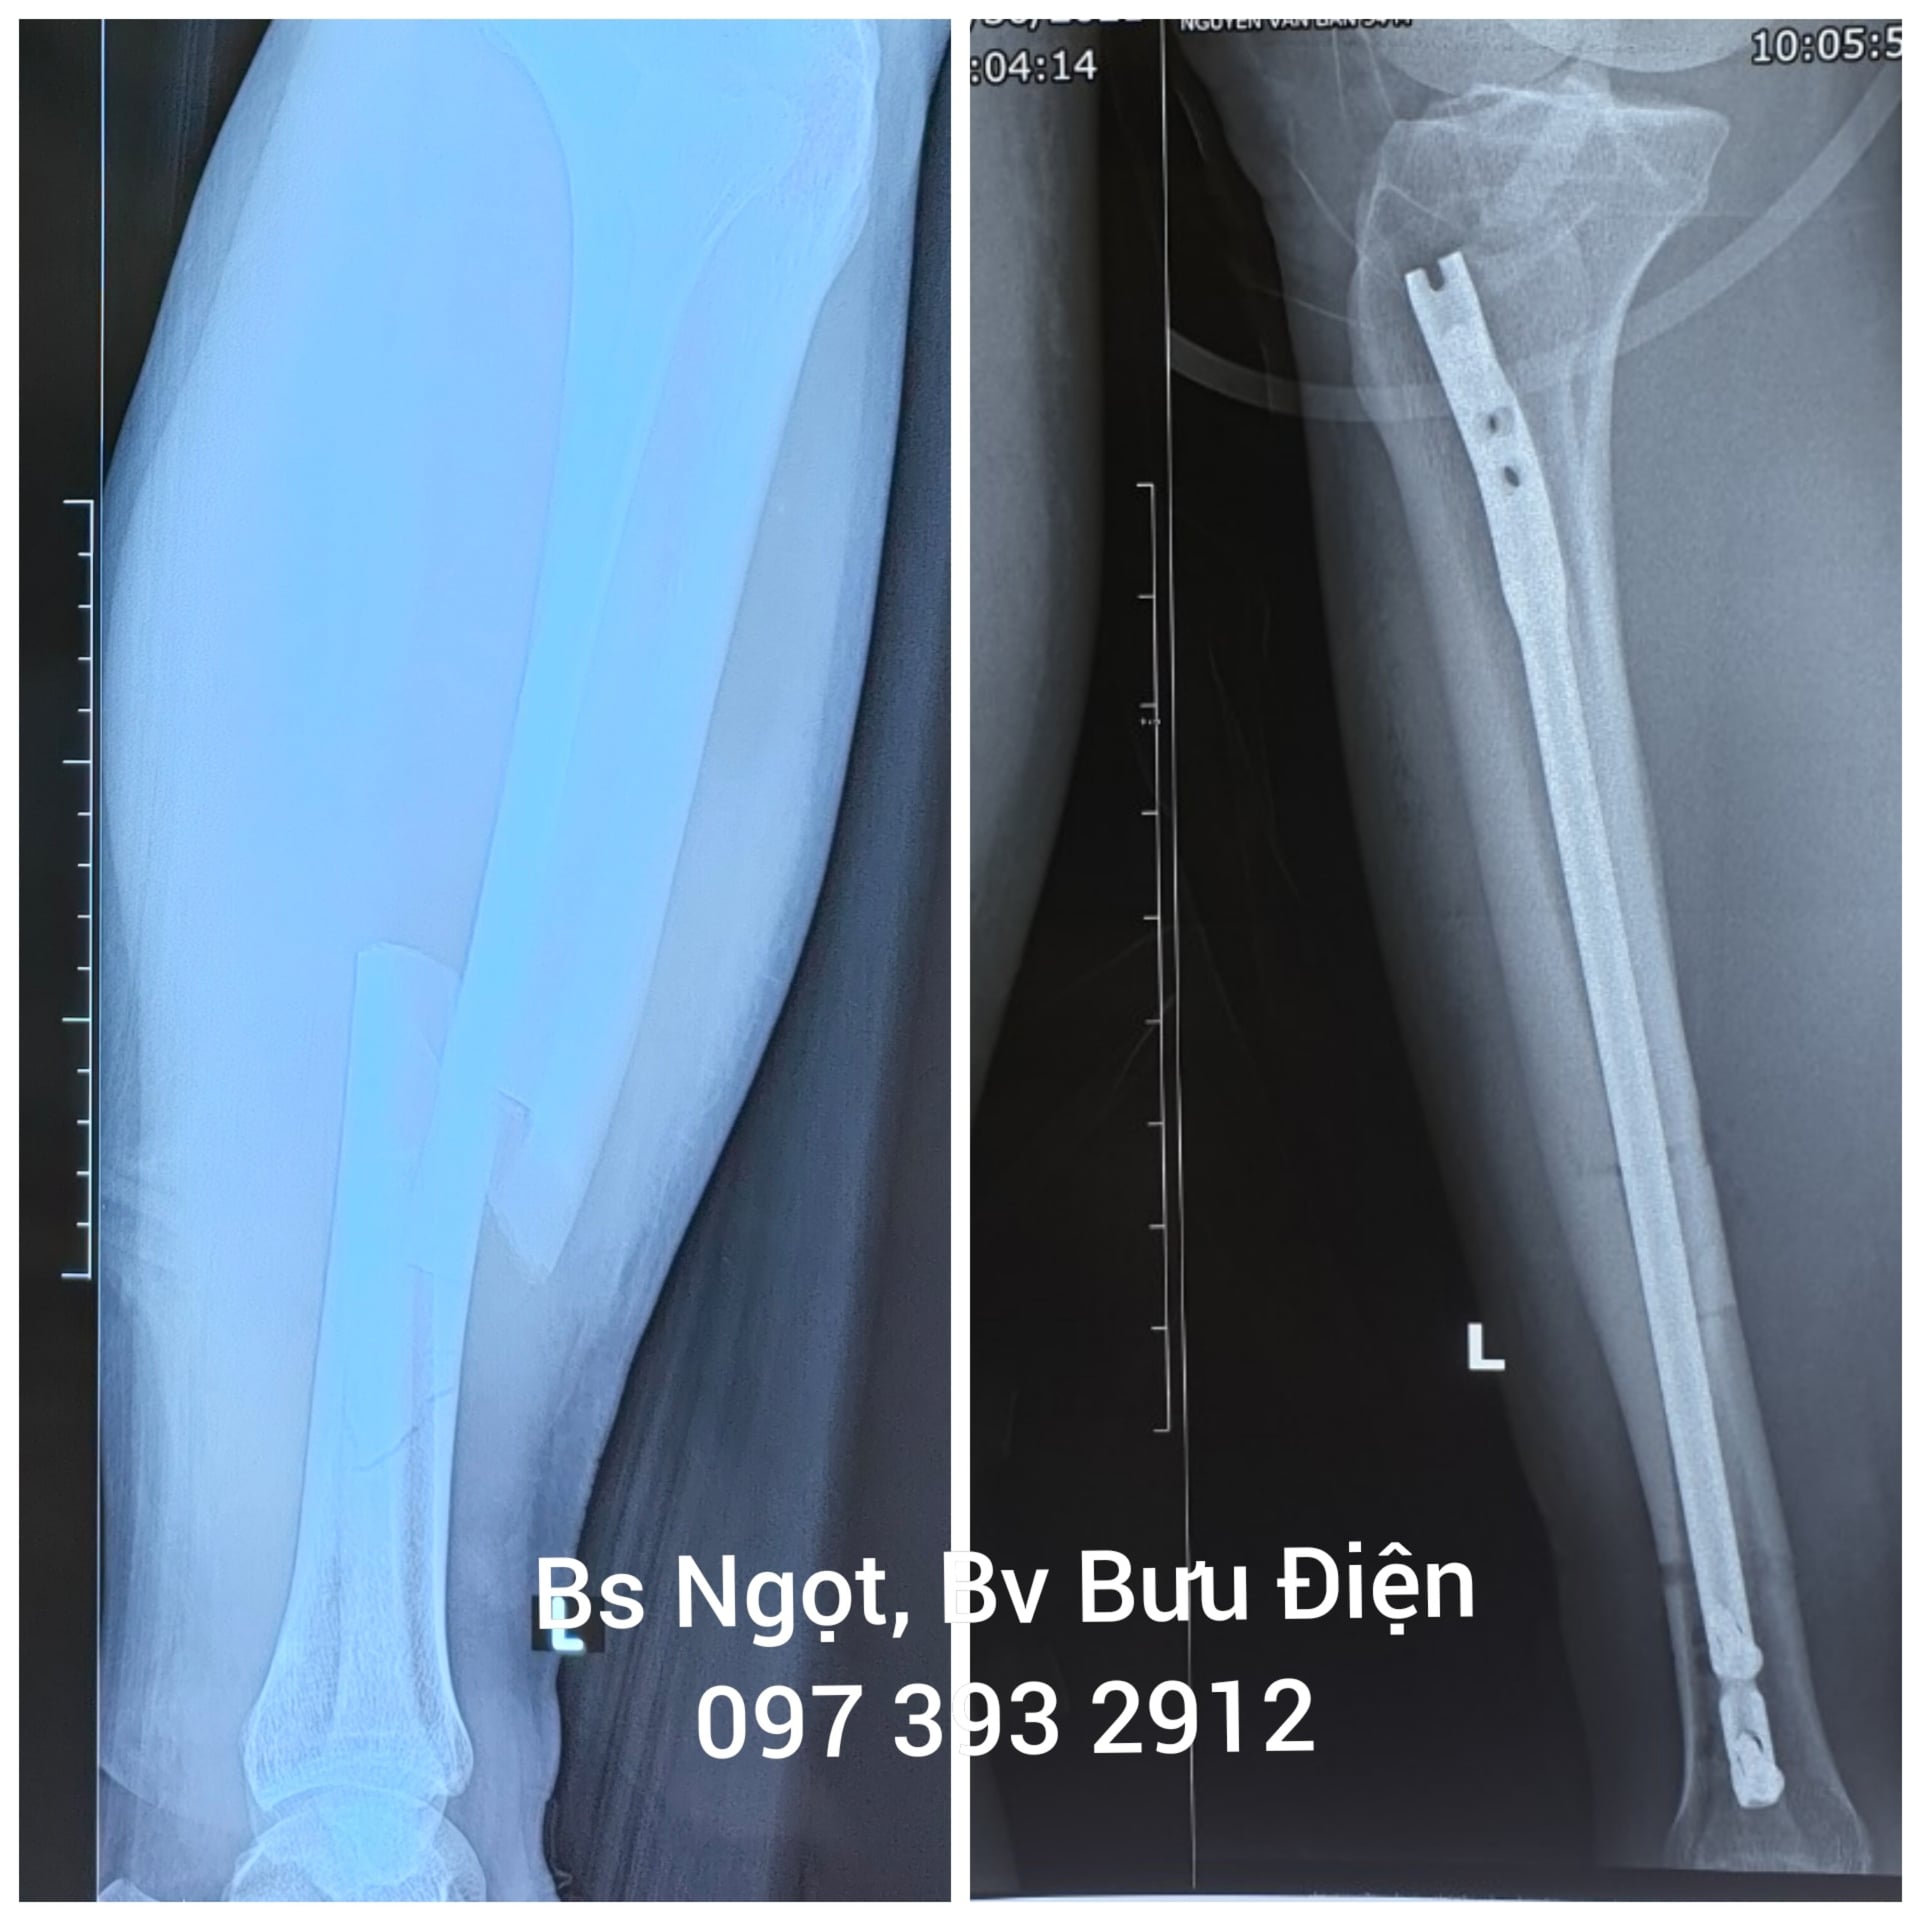

Phẫu thuật kết hợp xương chày bằng đinh nội tủy

Gãy thân xương chày hay gãy xương chày là sự gián đoạn cấu trúc toàn vẹn của xương chày do chấn thương trực tiếp hoặc gián tiếp gây đau và hạn chế vận động khớp gối và khớp cổ chân. Gãy thân xương chày ảnh hưởng nặng nề tới...